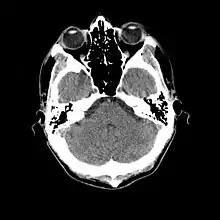

- Cranial computed tomography (CT, invented 1972) proved to be an excellent tool for diagnosing cerebral neoplasms in children, including those found in tuberous sclerosis.[46]

- MR was judged superior to CT imaging for both sensitivity and specificity. In a study of fifteen patients, it identified subependymal nodules projecting into the lateral ventricles in twelve patients, distortion of the normal cortical architecture in ten patients (corresponding to cortical tubers), dilated ventricles in five patients, and distinguished a known astrocytoma from benign subependymal nodules in one patient.[53]

- 1987

- MR imaging was found to be capable of predicting the clinical severity of the disease (epilepsy and developmental delay). A study of 25 patients found a correlation with the number of cortical tubers identified. In contrast, CT was not a useful predictor, but was superior at identifying calcified lesions.[54]

- Cortical tubers found on MR imaging corresponded exactly to the location of persistent EEG foci, in a study of six children with TSC. In particular, frontal cortical tubers were associated with more intractable seizures.[56]

- MRI with fluid attenuated inversion recovery (FLAIR) sequences was reported to be significantly better than standard T2-weighted images at highlighting small tubers, especially subcortical ones.[62][63]